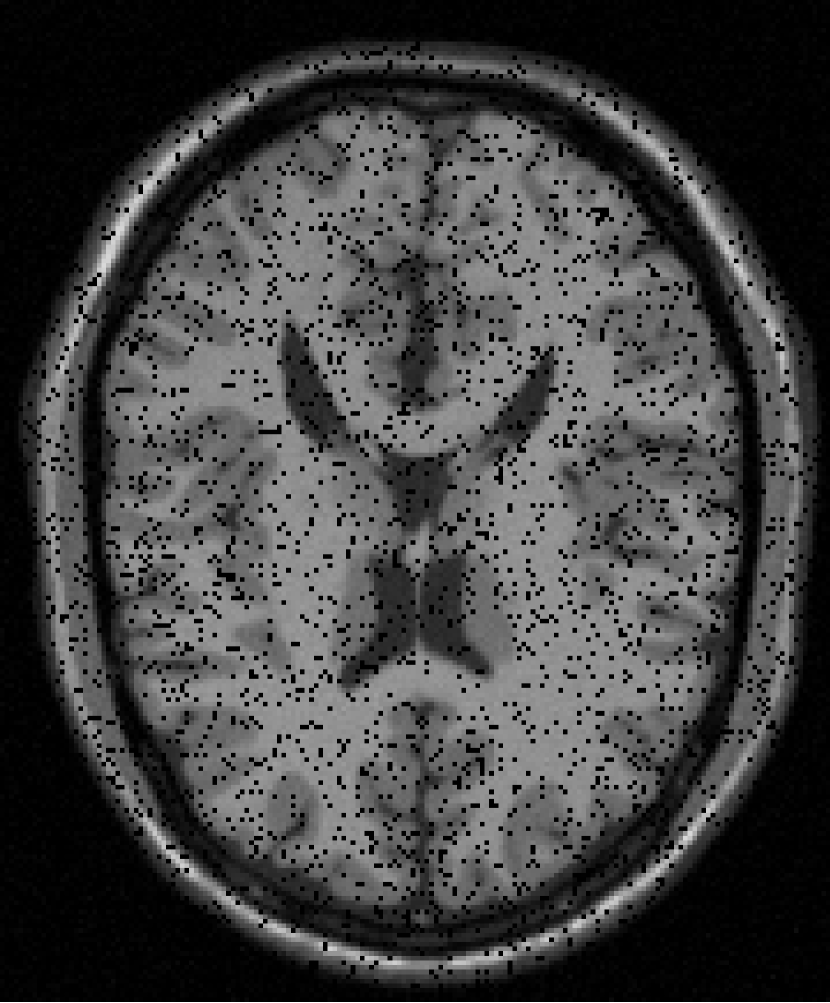

The resolution of the MRI volume dataset333http://graphics.stanford.edu/data/voldata/ is of size with 181 slices and we selected the 38th slice and the 88th slice for the experiment. We consider the case where entries are missing at random by sampling ratio . The GMM noise are set at .

From Figure 12 and Histogram 14, we can see that the effect of FPCA and SVT to restore images is very poor. The effect of VBMFL1 algorithm to restore images is good, but the running time is relatively long. SPG algorithm to restore the image effect and good running time is short. In summary, the SPG algorithm has the best recovery effect.